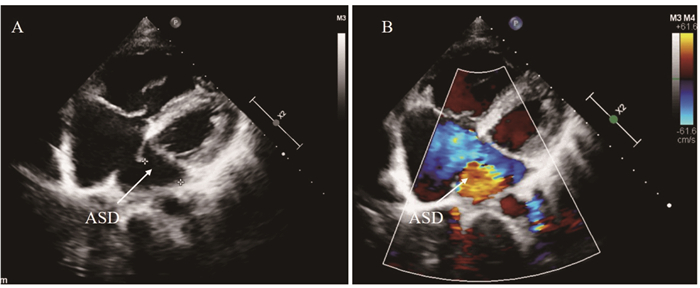

病例资料 女性, 25岁, 因“体检发现心脏杂音2年入院”, 平素一般体力活动可, 劳累后有胸闷气促, 伴有心悸, 无头晕、晕厥, 无下肢浮肿、口唇紫绀。患者入院前14天于门诊体检心超发现“房间隔缺损合并轻度肺动脉高压”, 为进一步手术治疗收治入院。既往史:无高血压等慢性疾病病史, 无手术史, 余无殊。入院时体格检查:体温36.5 ℃, 血压132/76 mmHg (1mmHg=0.133 kPa, 下同), 脉搏78次/分, 呼吸20次/分。神志清, 发育正常, 口唇指甲无发绀, 心前区可见隆起, 心尖搏动位于左侧第5肋间锁骨中线内侧, 搏动范围弥散。心尖区未扪及震颤及心包摩擦感, 心界不增大, 听诊心率78次/分, 律齐, 胸骨左缘2、3肋间可闻及Ⅲ级收缩期杂音。入院后心电图提示:窦性心率。经胸超声心动图(transthoracic echocardiography, TTE)提示(

A:Transthoracic echocardiogram showing a defect close to the ostium of the coronary sinus, which is a partially unroofed terminal portion of the coronary sinus.B:Color Doppler showing left to right shunt.

图 1 无顶冠状静脉窦综合征(UCSS)患者经胸超声心动图(TTE)图像

Fig 1 Unroofed coronary sinus syndrome (UCSS) shown by transthoracic echocardiography (TTE)